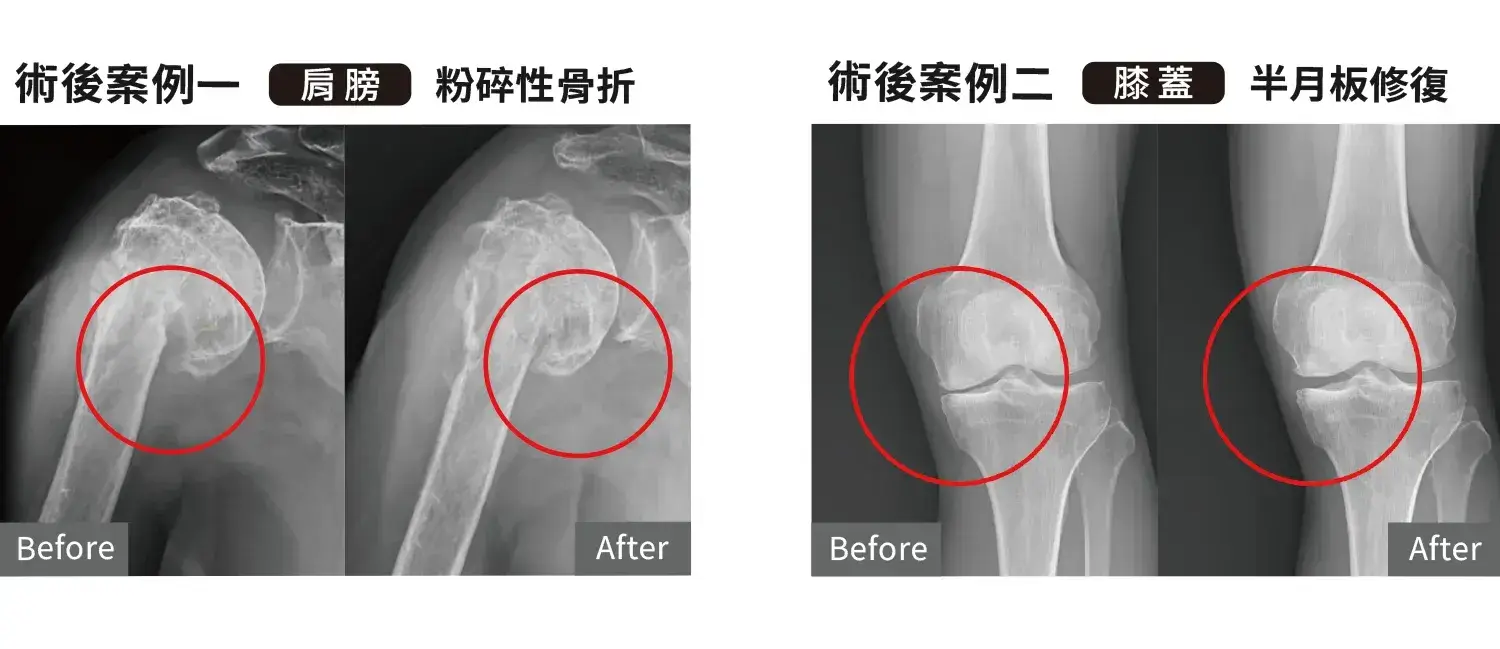

1. 骨科與運動醫學

2. 手術後修復

若是嚴重關節退化、完全韌帶斷裂或結構性破壞,仍可能需要手術治療。PRF也常用於手術後加速修復與提升癒合品質。